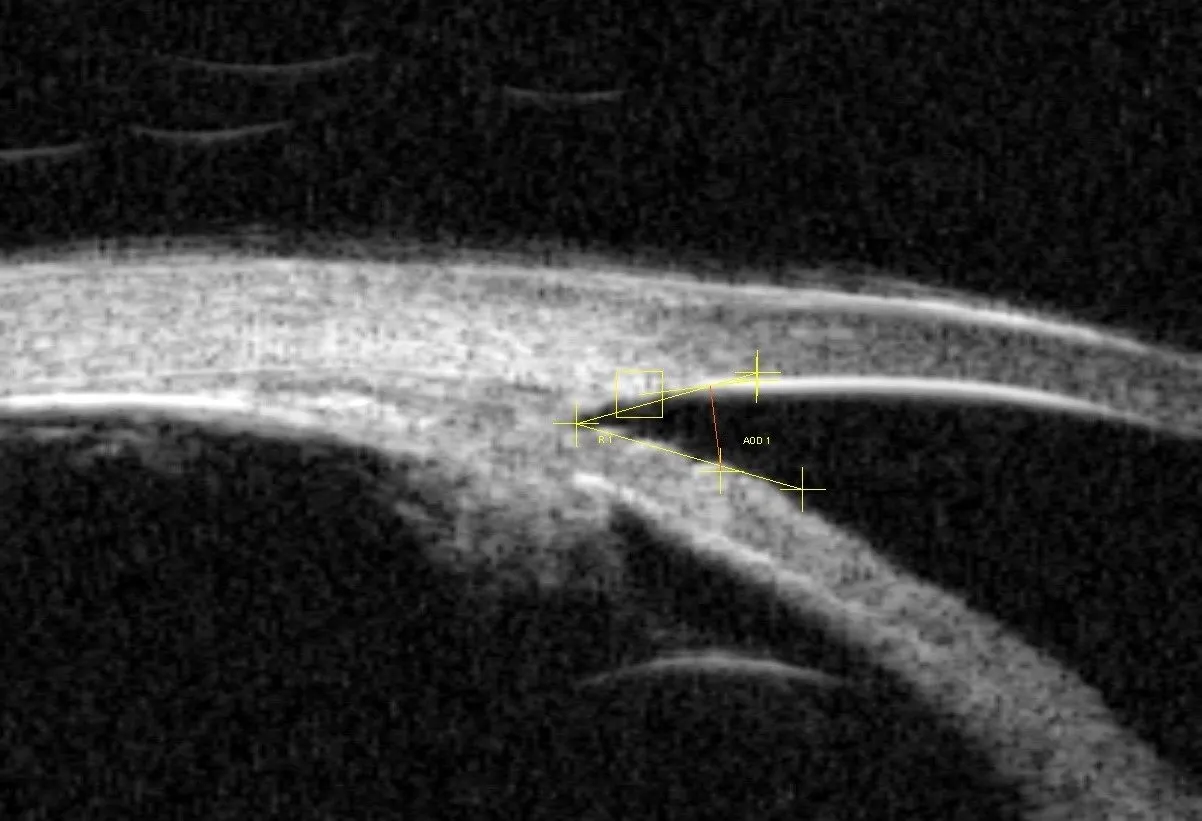

Optyczna koherentna tomografia (OCT) to nowoczesna technologia diagnostyczna, która zrewolucjonizowała wykrywanie jaskry. To badanie działa podobnie do USG, ale zamiast fal dźwiękowych wykorzystuje światło, tworząc bardzo szczegółowe przekrojowe obrazy struktur oka. OCT pozwala na precyzyjny pomiar grubości włókien nerwowych siatkówki oraz ocenę tarczy nerwu wzrokowego. Dzięki temu możemy wykryć bardzo wczesne, subtelne zmiany w nerwie wzrokowym, zanim jeszcze pojawią się ubytki w polu widzenia, co jest nieocenione w monitorowaniu postępu choroby.

Kolejnym istotnym badaniem jest gonioskopia, czyli badanie kąta przesączania. Kąt przesączania to struktura w oku, przez którą odpływa ciecz wodnista. Podczas gonioskopii okulista używa specjalnej soczewki, aby dokładnie obejrzeć ten kąt. Ocena jego szerokości i budowy jest kluczowa dla zrozumienia typu jaskry (otwartego lub zamkniętego kąta) i wyboru odpowiedniego leczenia. To badanie pozwala określić, czy problem z odpływem cieczy wynika z zamknięcia kąta, czy z innych przyczyn.